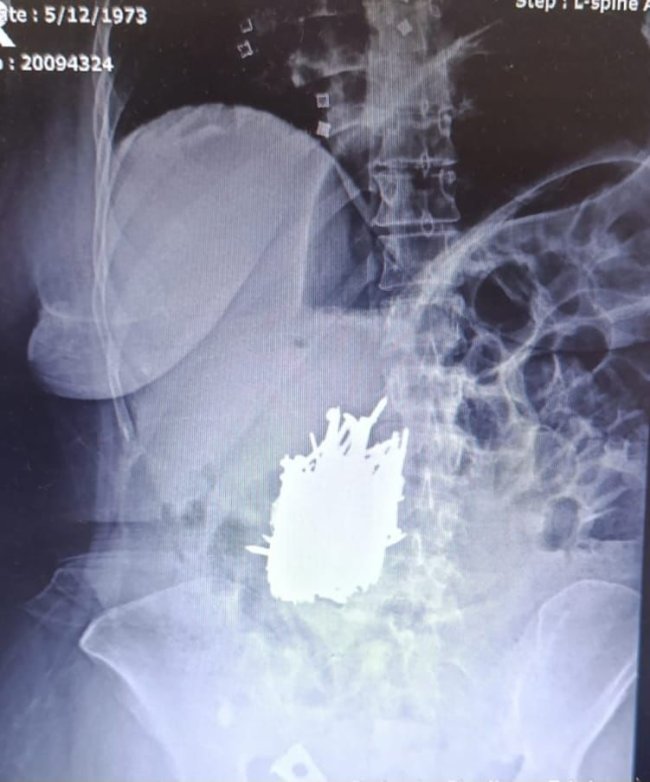

Karın ağrısı şikayetiyle hastaneye başvuran kadının midesinden 1 kiloya yakın çivi, inşaat demiri, kolye, toka gibi metal cisim çıkarıldı.

Mersin’in Erdemli ilçesinde zihinsel engelli olduğu bilinen A.K. isimli kadın karın ağrısı şikayetiyle hastaneye başvurdu. Hastaya yapılan tetkik sonucunda kadının midesinde çok sayıda metal cisim olduğu tespit edildi. Hasta, Genel Cerrahi Uzmanı Dr. Can Terzier ve ekibi tarafından acilen ameliyata alındı ve midesinden yaklaşık 1 kilo ağırlığında çivi, inşaat demiri, kolye, toka gibi çok sayıda metal cisim çıkarıldı.